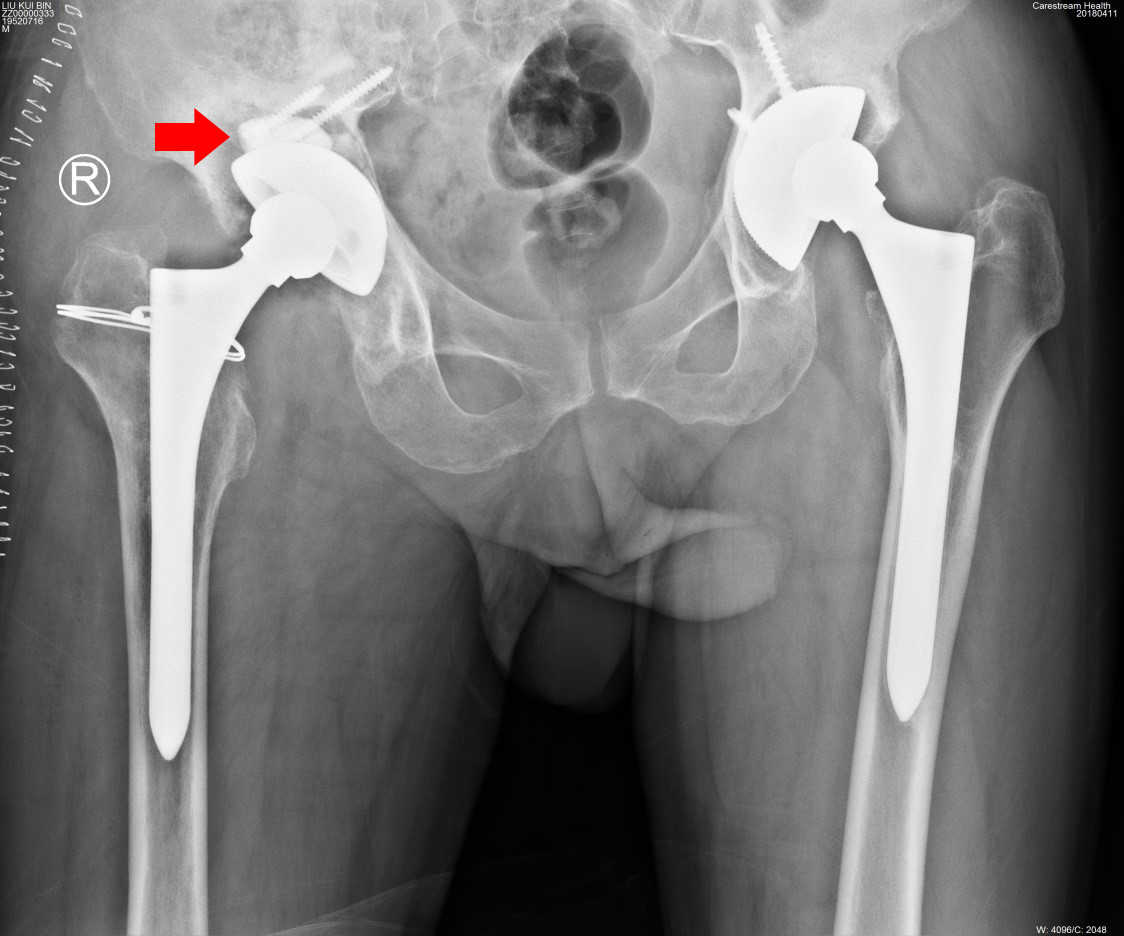

经过全面检查,刘大爷确实是“右髋关节置换术后假体松动”,唯一的解决办法就是翻修手术,但手术难度非常大。张敬东主任耐心详细地向刘大爷交待着病情,把手术的难度一一讲述清楚:由于假体松动时间较长,髋臼侧骨量低,尤其是在髋臼上壁存在空腔型骨缺损,直接影响手术术式及治疗效果;7年前的假体直径60mm,属于大杯,翻修手术时需要直径更大的型号,才能保证术中假体安装的稳定性,然而大杯就面临着更大的骨量丢失;初次置换使用的假体型号特殊,原厂家已停产,其他厂家不匹配。张主任说:“如果要做这个翻修手术,既要保证刘大爷骨量不丢失太多,又要保证即刻及长期的稳定性,还要找到能与刘大爷匹配的假体。”

医者仁心,以德为先。看着刘大爷充满渴望的双眼,张主任决定克服一切,用精湛的技术迎难而上,为刘大爷做这个极具挑战性的手术。于是,张主任同步开始着一系列的准备工作。一方面联系假体生产厂家,说明情况,请厂家想尽一切办法解决假体问题;另一面组织全科室多次反复地讨论刘大爷的病情,最终制定出了最佳手术方案:只翻修髋臼侧,选用强生公司髋臼垫块(GRIPTION TF)系统解决髋臼缺损问题,保留刘大爷股骨柄假体及原球头,术中尽量使用生物固定,以保存刘大爷的骨量及术后恢复。